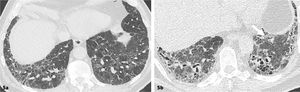

Patrón UIPDistorsión de la arquitectura pulmonar caracterizada por la presencia de opacidades reticulares, bronquiectasia/bronquiolectasias por tracción y panalización, de predominio basal (gradiente ápico-basal) y subpleural. No deben existir características atípicas. Este patrón tiene una correlación del 90% con los hallazgos histopatológicos de UIP5,11. (Figuras 2.1 y 2.2).

Enfermedad pulmonar intersticial fibrótica con patrón UIP

Distorsión de la arquitectura pulmonar bilateral caracterizado por reticulaciones y bronquiectasias por tracción de distribución asimétrica, de predominio subpleural, Se identifican áreas de panalización y gradiente ápico-basal (reconstrucción sagital 2d).